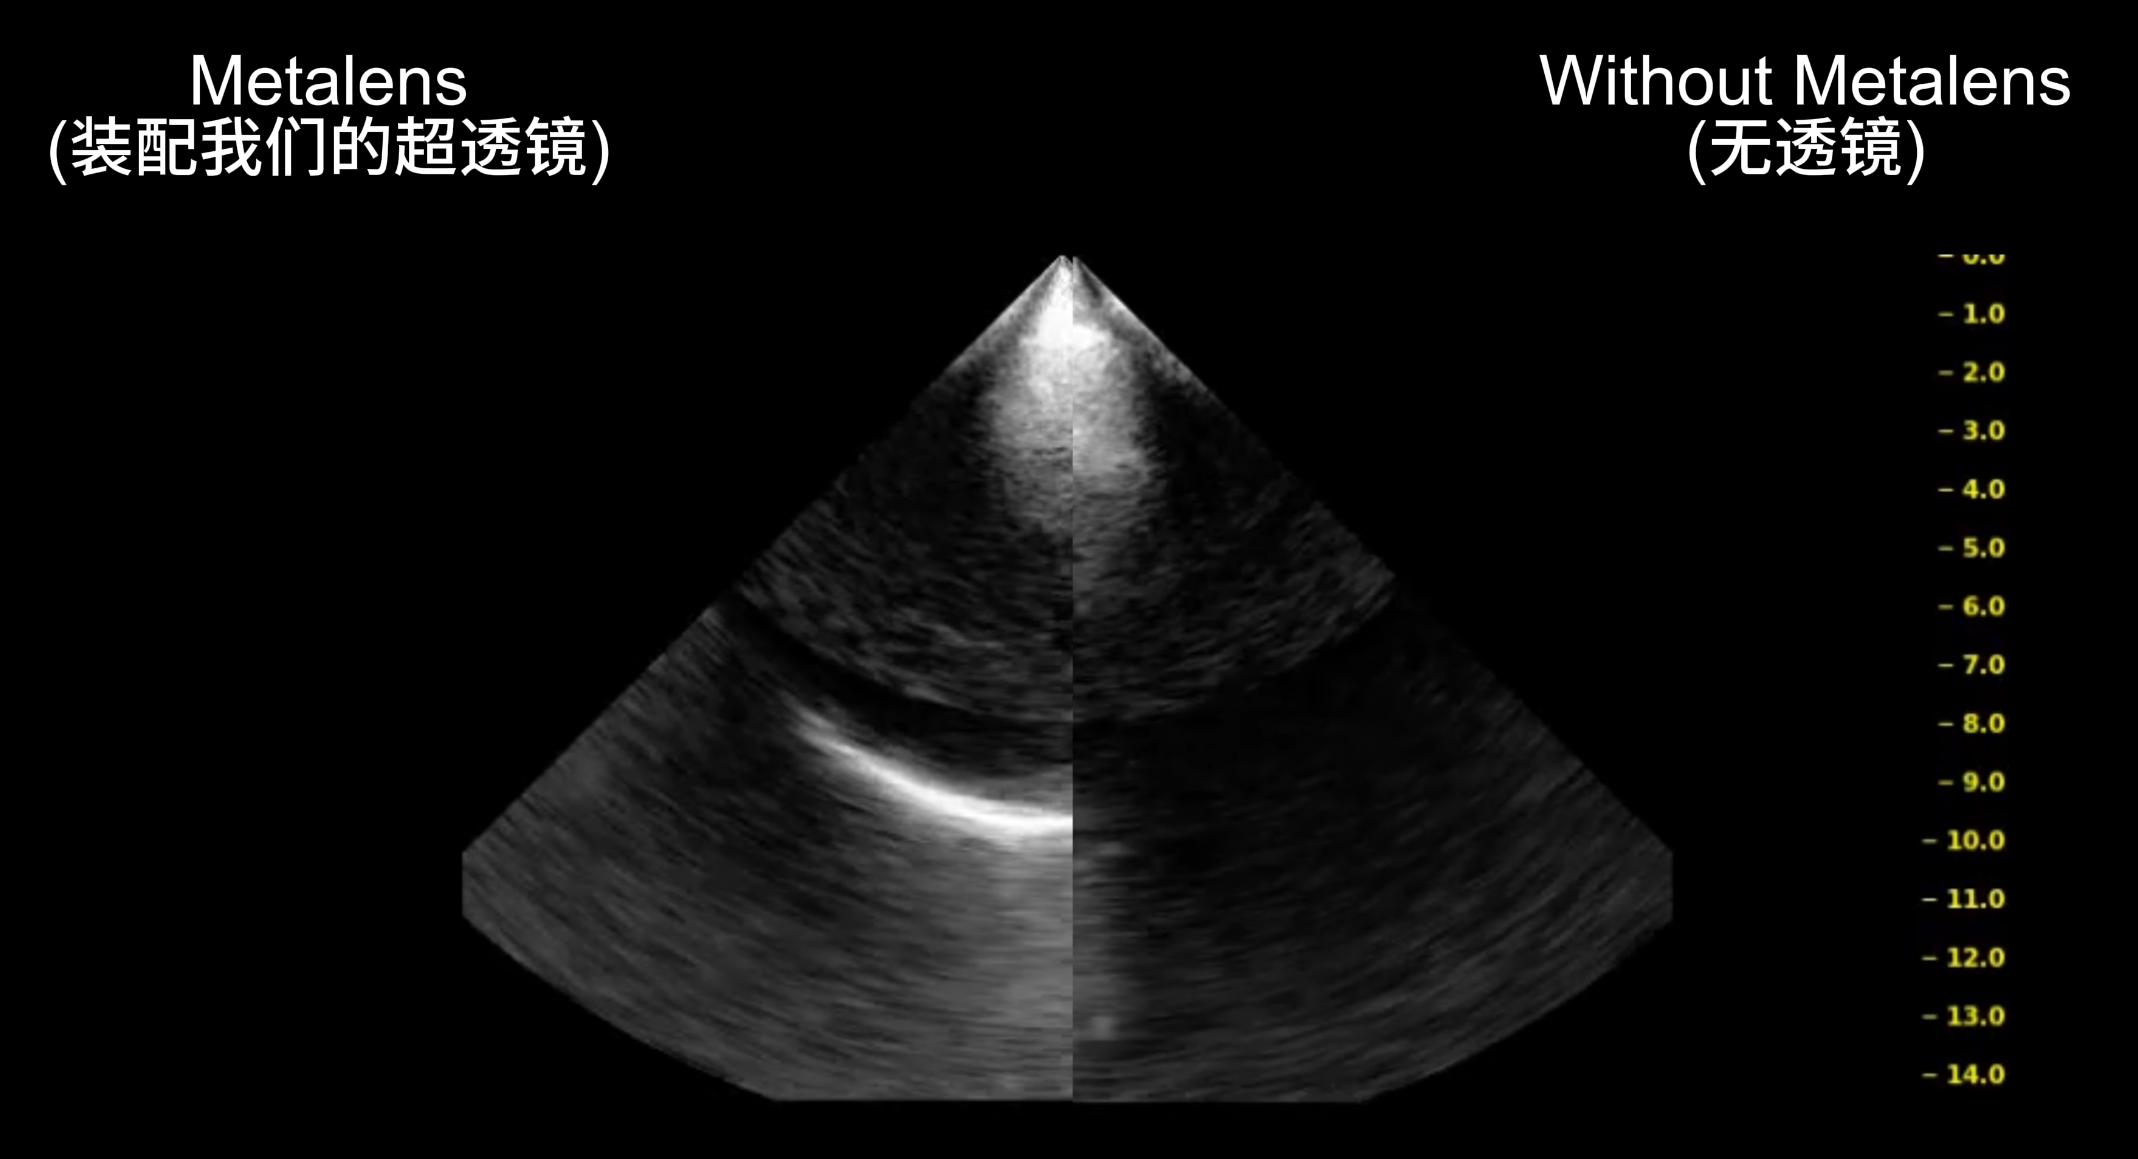

Our group were proud to demonstrate their latest research breakthroughs during HKU Innovation Week on 2025 Oct 14. PhD student Jin Yihan, MSc student Zhu Zejia, Postdoctoral Fellow Dr. Dong Erqian, and group leader Prof. Nick Fang presented a novel acoustic metalens platform designed to overcome fundamental limitations in ultrasound applications. This breakthrough technology, powered by an in-house designed 64-element ultrasound probe, enables precise beam steering for challenging scenarios including transcranial imaging, targeted neuromodulation, and transcostal imaging. The showcase highlighted the group’s progress in developing next-generation, non-invasive diagnostic and therapeutic tools.